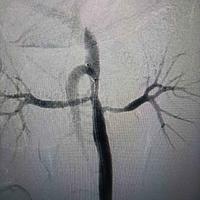

髂骨肿瘤

髂骨肿瘤...